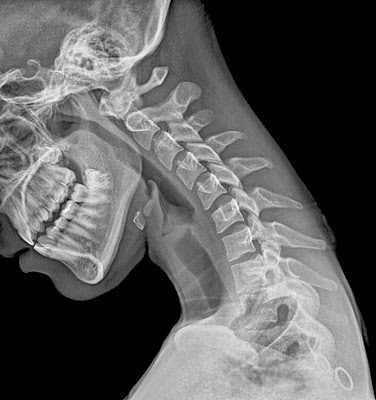

| c1 (top) – c7 (bottom)* |

There are less protrusions and more gaps toward the top, and more bony points and stackable processes, limiting movement toward the bottom.